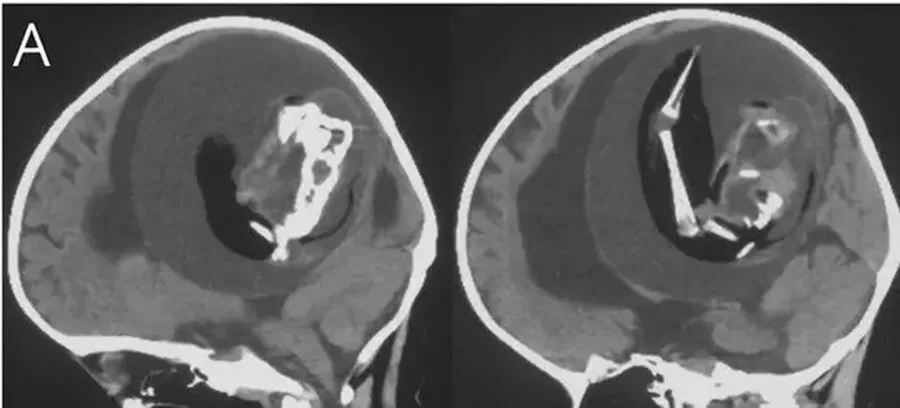

Şangay şehrinde yaşanan olağanüstü bir olay, 1 yaşındaki bir bebeğin kafatasında doğmamış ikizinin bulunmasıyla gündeme oturdu. Bebeğin geniş kafatası ve motor becerilerindeki sorunlar nedeniyle hastaneye getirilmesi sonrasında yapılan incelemeler akıl almaz bir gerçeği ortaya çıkardı. Amerikan Nöroloji Akademisi'nin 'Neurology' dergisinde yayınlanan bir makaleye göre yapılan çeşitli görüntüleme yöntemleriyle incelenen bebeğin beyninin içinde doğmamış ikizi olduğu belirlendi. Bu olay, tıp literatüründe sadece 18 kez rapor edilmiş bir durum olarak kayıtlara geçti. Araştırmacılar, bebeğin kafatasında sıkışan ikizin, anne karnında yeterince gelişemediği ve kardeşinin kafatasına sıkıştığı sonucuna vardı. Beyinde sıvı birikimi ve sıkışma tespit edilen bebeğin, aslında ikiz kardeşiyle birlikte anne karnında geliştiği ortaya çıktı. Doktorlar, fetüsün üst uzuvlarının kemiklerinin ve tırnaklarının rahim içinde aylarca büyümeye devam ettiğini açıkladı.

Ameliyatla Çıkarılan 10 Santimlik Fetüs

Yaklaşık 10 santimlik ikiz, özel bir ameliyatla bebeğin kafatasından çıkarıldı. Bu olay, tıbbi literatürde kayıtlara geçmiş 18 benzersiz vakadan biri olarak öne çıkıyor. İkiz fetüsün çıkarılmasıyla birlikte bebeğin sağlık durumunda olumlu gelişmeler gözlendi.